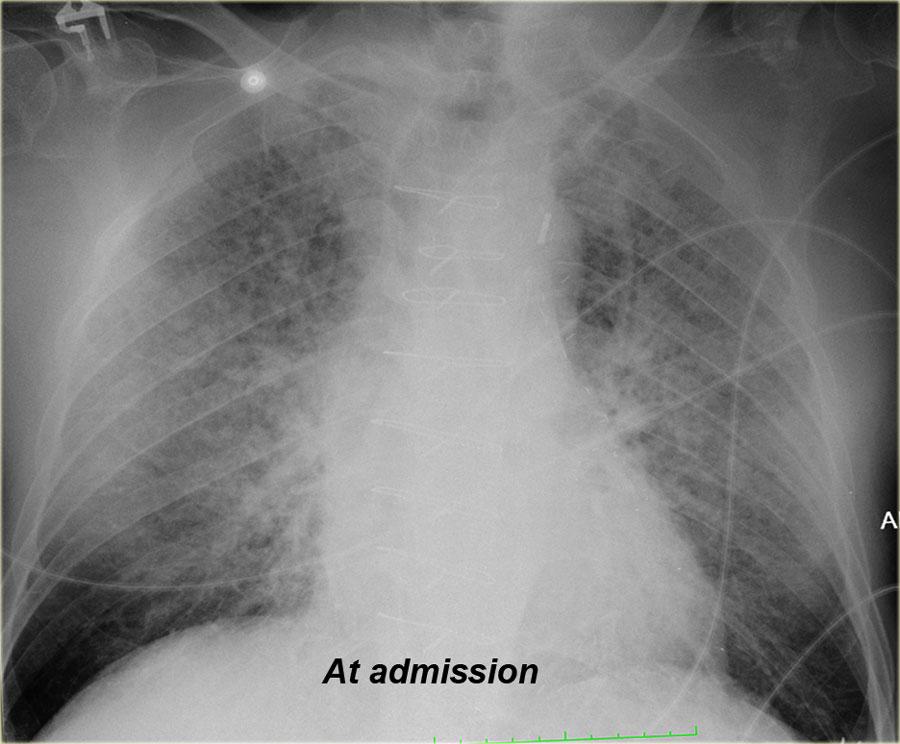

Bên trái là hình ảnh một bệnh nhân khác với phù phế nang lúc nhập viện, đã được giải quyết sau điều trị.

Khi bạn cuộn qua các hình ảnh và so sánh qua lại, bạn sẽ nhận thấy sự khác biệt về độ rộng cuống mạch máu và sự phân bố lưu lượng máu phổi.